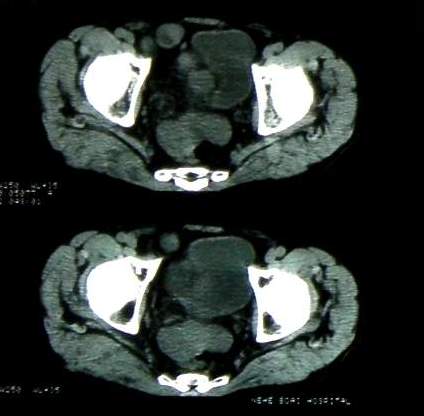

男 60岁,下腹部肿块半年余

前列腺肥大,密度不均。伴盆腔实性肿块。考虑前列腺癌伴盆腔转移。建议增强扫描。

考虑来源于肠道的肿瘤,乙状结肠?询问排便情况

盆腔恶性占位,间质瘤可能性大

乙状结肠间质瘤

盆腔恶性占位,间质瘤可能性大。

病理结果:肠系膜肉瘤

病灶形态不规则,偏心性裂隙样坏死,支持恶性病变。来源不好定。感谢反馈结果--肠系膜肉瘤。